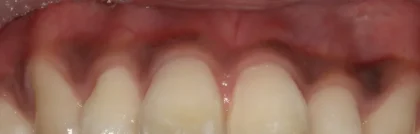

健康な状態: 淡いきれいなピンク色(ライトピンク)をしています。

注意が必要な状態: 炎症が起きると赤みを帯びたり、血流が滞る「うっ血」という状態になると、暗い赤紫色に見えることがあります。

健康な状態: 全体的にキュッと引き締まっています。特に注目したいのが、歯と歯の間を埋めるシャープな三角形の部分。これは「歯間乳頭(しかんにゅうとう)」と呼ばれ、健康のバロメーターです。

注意が必要な状態: 歯周病などで炎症が起きると、この歯間乳頭が丸みを帯びてブヨブヨと膨らみます。これが「腫れている」状態です。